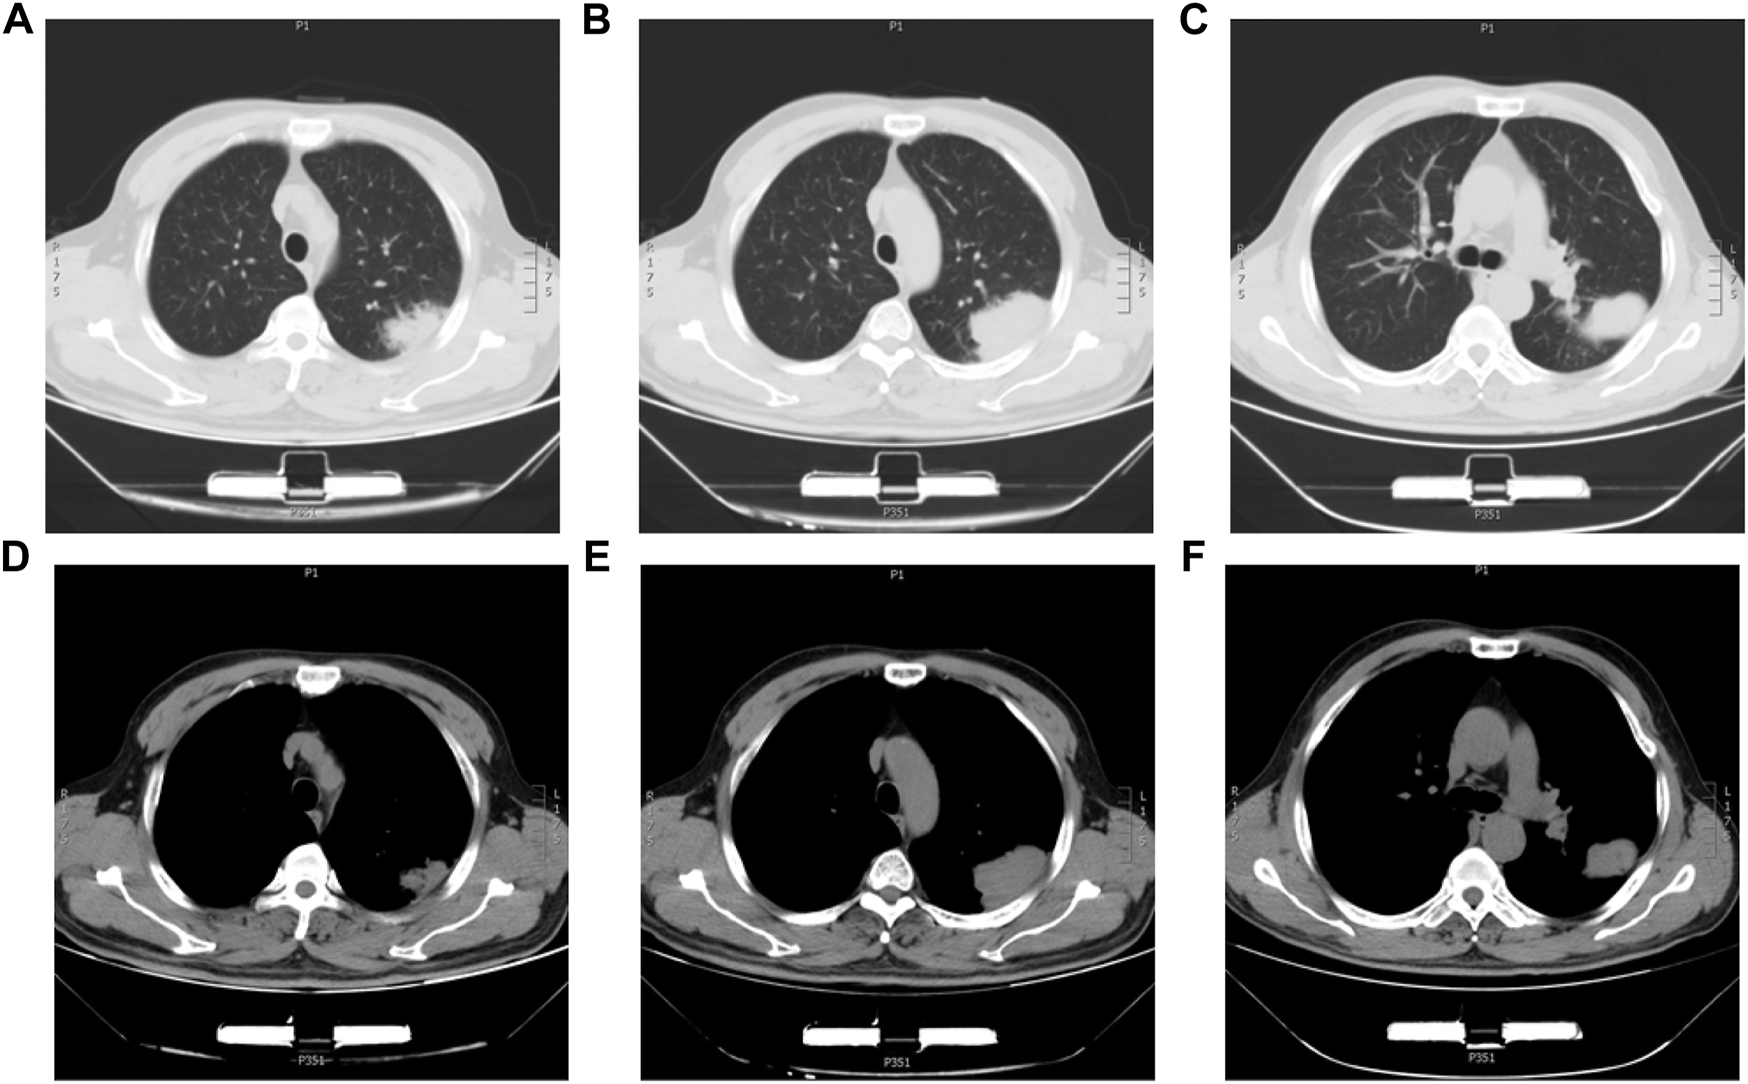

The 63-year-old male patient was admitted to the First Affiliated Hospital of China Medical University on 5 September 2018, with intermittent dyspnea and occasional chest pain. The chest-CT scan showed a 7.5*5.5 cm2 mass in the left upper lung with local pleural wrinkling and slightly enlarged lymph nodes in the mediastinum (Figure 1). Before the operation, no metastasis was found in brain CT or bone nuclide scan, while serum carcinoma embryonic antigen (CEA) and neuron-specific enolase (NSE) were slightly elevated, and AFP was in the normal range. On 19 September 2018, the patient underwent left upper lobe resection and mediastinal lymph node dissection. Referring to the preoperative abdominal B-ultrasound examination and postoperative abdominal B-ultrasound examination, 3 months after the surgery, there was no obvious abnormality in the liver, and the patient’s status was average with no history of hepatitis, alcohol abuse, exposure to radiation, or toxins. Meanwhile, he had no symptoms of liver cirrhosis such as spider-burst, liver palms, or hepatojugular reflex. We measured the patient’s plasma AFP levels 4 days before surgery, 1 day after surgery, and 3 months after surgery. The results of AFP were 11.02 ng/ml, 13.11 ng/ml, and 9.21 ng/ml, respectively. Given the patient’s symptoms, personal history, physical examination, preoperative examination, and immunohistochemical staining results of postoperative pathology, the patient was diagnosed with HAL. Meanwhile, there was no metastatic lesion in the mediastinal lymph nodes or adjacent tissue or organs; thus, the post-operative staging is T4N0M0. The patient recovered well after surgery and was discharged from the hospital one week later. Subsequently, a 300 gene-panel genomic testing was conducted, which contained targeted drug-related genes and chemotherapy drug-related genes. Nevertheless, no targeted drug-matched gene mutation was found in the testing. The patient did not receive radiotherapy or chemotherapy after surgery and died of an accidental cerebral hemorrhage six months later.

FIGURE 1

Chest CT images of the HAL patient. (A,B,C) CT images of the lung window with a lung mass in the left upper lobe. (D,E,F) CT images of the mediastinum window with a lung mass in the left upper lobe.